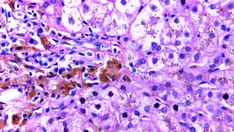

Liver biopsy, with biochemical determination of hepatic iron concentration and calculation of the hepatic iron index and histologic evaluation with iron staining (Perls Prussian blue)